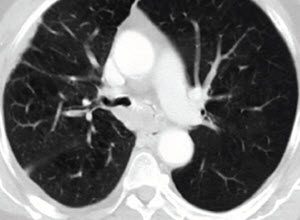

A 75-year-old man who had advanced stage lung cancer presented with worsening dyspnea and productive cough. Under bronchoscopic exam, the right middle lobe (RML) had a 90% stenosis with evidence of post-obstructive pneumonia.